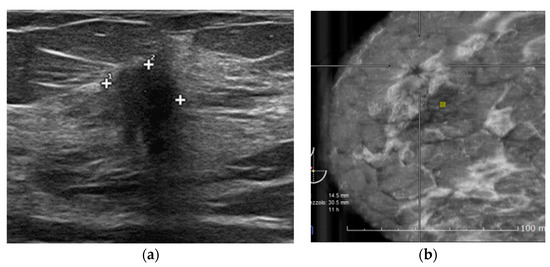

2.2. HHUS Examination

2.3. ABVS Execution

2.4. ABVS Interpretation